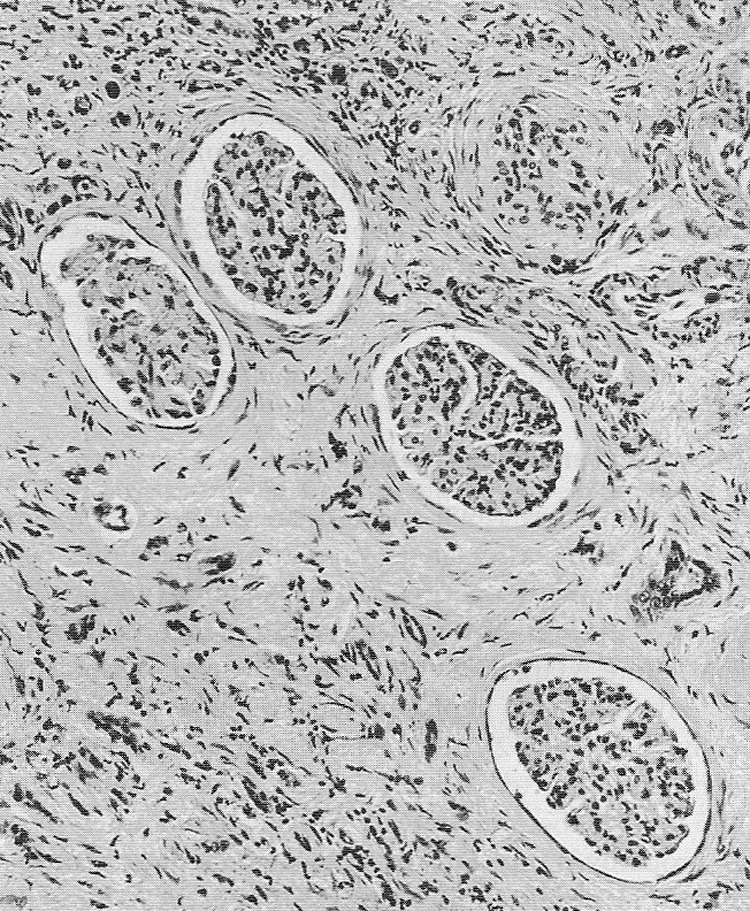

Основным патогенетическим механизмом БЭН считается хроническое воздействие аристолоховой кислоты, содержащейся в семенах растения Aristolochia clematitis, которые случайно попадают в зерновые культуры в эндемичных районах. После метаболизма в организме это вещество вызвывает характерные генетические мутации и приводит к повреждению почечных канальцев. Данный процесс провоцирует прогрессирующий интерстициальный фиброз с атрофией канальцев и склерозом клубочков [1].

БЭН характеризуется прогрессирующими патологическими изменениями в почках, которые развиваются поэтапно. На ранней стадии заболевания поражаются преимущественно наружные отделы коркового слоя, где наблюдается расширение мезангия клубочков и утолщение их базальных мембран, сопровождающееся дистрофическими процессами в проксимальных канальцах [3].

По мере прогрессирования болезни патологические изменения становятся более выраженными. В субклинической стадии продолжается утолщение базальных мембран, причём в дистальных канальцах этот процесс менее интенсивен, чем в проксимальных. Одновременно развивается начальный интерстициальный склероз и появляются характерные сосудистые изменения - утолщение стенок артериол с неравномерным сужением их просвета [3].

В терминальной стадии происходит резкое уменьшение размеров почек (их масса может снижаться до 40 грамм при норме 115-170 грамм). Структура почечной ткани значительно изменяется: большинство канальцев коркового вещества полностью атрофируются, теряя эпителиальную выстилку, а повреждённые клубочки и канальцы замещаются соединительной тканью. Эти необратимые изменения приводят к полной утрате функциональной активности поражённых почек [3].

Биопсия почки с гистологическим исследование биоптата выявляется характерные морфологические изменения [1].